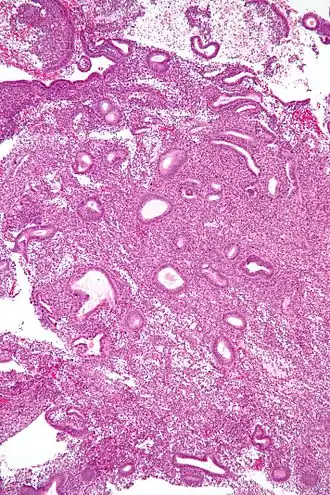

|  Micrograph showing an  endometrial biopsy with simple endometrial hyperplasia, where the gland-to-stroma ratio is preserved but the glands have an irregular shape and/or are dilated. H&E stain. | |